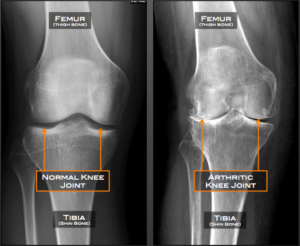

Knee osteoarthritis is a degenerative process that occurs when the cartilage layer on the end of two articulating bones begins to wear down allowing for those bone to come into direct contact with one another. You may have heard some medical providers describe this to you as “bone-on-bone”. This often leads to pain and osteophyte (bone spur) formation, which compounds this disease.

For the example of the knee, this means that the articular cartilage layer between the tibia (shin bone) and the femur (thigh bone) has worn down. The cartilage that has been damaged has an extremely low capacity to regenerate itself. If not properly addressed, this progressive degeneration can continue over time. Pain, morning stiffness, decreased range of motion, bony enlargement, inflammation, crepitus, and decreased function are some of the symptoms associated with osteoarthritis. Osteoarthritis can occur in joints throughout the body, however it is most common in the knees and hips.